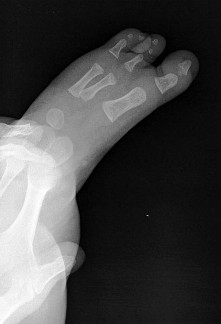

A 13-year-old girl sustains an ankle injury during a soccer match. Radiographs reveal an isolated Salter-Harris III fracture of the anterolateral distal tibial epiphysis (Tillaux fracture). Which of the following describes the anatomical sequence of distal tibial physeal closure that predisposes adolescents to this specific fracture pattern?

A 13-year-old female sustains a fracture of the anterolateral aspect of her distal tibial epiphysis after an external rotation injury. This fracture pattern (Tillaux fracture) occurs specifically due to the asymmetrical closure of the distal tibial physis. In what sequence does the normal distal tibial physis close?